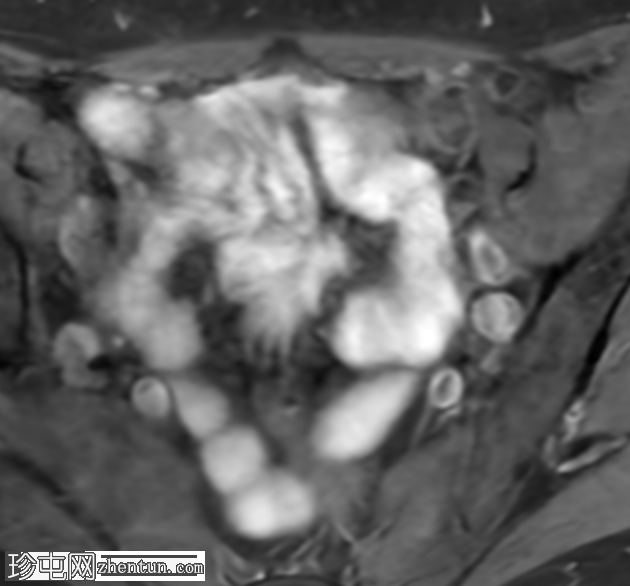

轴位T1加权像

脂肪抑制像

盆腔MRI显示右侧卵巢解剖位置可见一边界清晰的卵圆形肿块。该病灶由囊性和实性成分组成。囊性部分壁薄,在T2加权像上呈均匀高信号,在T1加权脂肪抑制序列上呈低信号,无对比剂增强。该实性成分的信号特征与正常卵巢组织相似,DWI成像未见扩散受限,静脉注射造影剂后未见异常强化。

此外,在子宫左侧壁可见一管状薄壁囊性结构,延伸至同侧髂外血管,末端呈盲端。该结构在T2加权像上呈均匀高信号,在T1加权脂肪抑制序列上呈低信号,且无造影剂强化。

本例中,盆腔MRI显示,患者右侧卵巢解剖位置存在一个边界清晰的附件肿块,该患者有20年前行双侧输卵管卵巢切除术的病史。该病灶包含囊性和实性成分,其中实性部分表现出与正常卵巢组织相似的信号特征。无扩散受限和无可疑的增强扫描强化提示排除恶性病变。这些影像学特征结合相关的手术史进行解读,符合残留卵巢组织的特征,支持卵巢残留综合征的诊断。此外,还发现对侧子宫左侧延伸出一个管状薄壁囊性结构,末端呈盲端。其形态、信号特征和无强化表现符合输卵管残端或输卵管残端积水,这是输卵管切除术后常见的术后表现。附件残余的存在进一步支持术后病因,而非原发性妇科肿瘤

主要鉴别诊断包括腹膜包涵囊肿、子宫内膜异位症相关囊肿和附件肿瘤。腹膜包涵囊肿通常位于腹膜腔内,不含类似卵巢组织的实性成分。子宫内膜异位囊肿通常在T1加权像上表现为高信号,T2加权像上出现阴影,并具有其他特征性MRI表现,而本例4中均未见这些表现。鉴于无扩散受限、无可疑强化以及实性成分的良性影像学表现,肿瘤性病变的可能性较小。